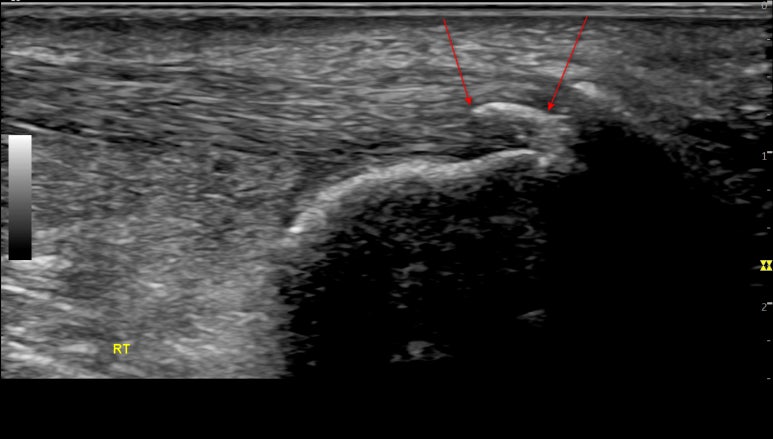

영상에서

족태양경근은 깊이에 따라

아킬레스건, 장무지굴근, 종골, 거골 등

다양한 구조물이 보입니다.

그 중에

아킬레스건(ACH T)은흰색 줄무늬 섬유 패턴으로보이는데요.

위 환자분은

아킬레스건이

많이 부어있으셨고요.

화살표친까만색 틈이 보이시나요?

정형외과에서

아킬레스건 염증이 심해지며

찢어지고 있다고

들으셨다고요.

힘줄이 완전히 파열되면

수술도 고려해봐야 됩니다.

일반적으로 한국인의 아킬레스건은

5mm를 넘지 않는데요.

이 환자분은9mm 정도가 나옵니다.2배 가까이부은 상태죠?

오랜 기간동안

만성 염증에 시달렸던 것을

알 수 있습니다.